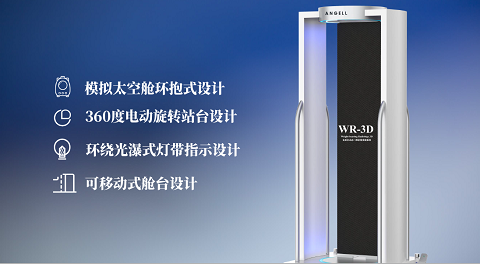

在DR设备的选择上,当地政府相关部门与卡若区人民医院基于医院的临床科室需求,定位于采购多功能的动态数字化X线设备,减少医疗资源的浪费,提升设备配置的效率。经过前期的详细设备功能与图像考察,在公开、公平、公正的招标遴选程序下,亿万28入口网页版-亿万28网页在线玩-万28官网下载最新版-亿万e网址pg-亿万28pg电子-亿万28赏金女王-亿万28娱乐科技动态多功能诊断专用DR—腾灵进入昌都卡若区人民医院,开启了其服务藏区百姓的健康使命。

图4:腾灵——动态多功能诊断专用DR

作为一款动态多功能诊断专用DR设备,腾灵支持高清摄片、透视摄影、造影摄影、全脊柱摄影、全下肢摄影检查于一身,满足低人口密度地区的多种数字化X线摄影检查需求。在卡若区人民医院,每天大约有60人左右的检查人次,来自于一区十县 24个镇118乡的藏区百姓,腾灵在过去近一年的服役中赢得了放射科主任及主管技师的一致认可。